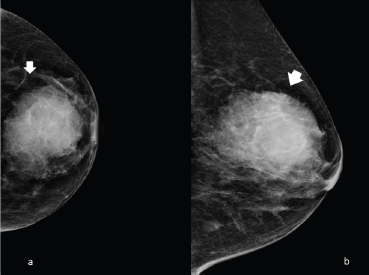

The typical mammogram manifestation of granulocytic sarcoma is the presence of a large, non-calcified irregular mass with poorly defined ‘feathery’’ margins [10, 11], as shown in Figures 1 and 2.

Figure 1. Left side full-field digital mammography of a 70-year-old patient presenting a unilateral breast mass subsequently identified as a MS. (a): Cranio caudal and (b): mediolateral oblique projection, showing a noncalcified ill-defined radiopaque mass with poorly defined ‘feathery’ margins (arrow).

Figure 2. Right side full-field mammography of a 40-year-old patient presenting a unilateral breast mass subsequently identified as a MS. (a): Cranio caudal and (b): mediolateral oblique projection, showing a noncalcified ill-defined radiopaque mass with poorly defined ‘feathery’ margins (arrow).